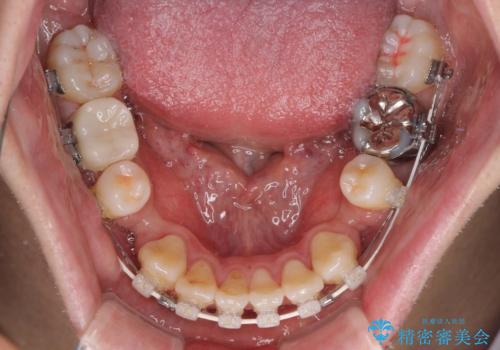

装置は、透明感のあるクリアブラケットとホワイトコーティングされたワイヤーを使用した、目立ちにくい審美装置を選択。

周囲に気づかれにくく、日常生活にも自然に溶け込みます。

治療期間は約2年。

少しずつ前歯を後ろに下げていくことで、横顔のラインが整い、口元の“出っ張り感”が解消。